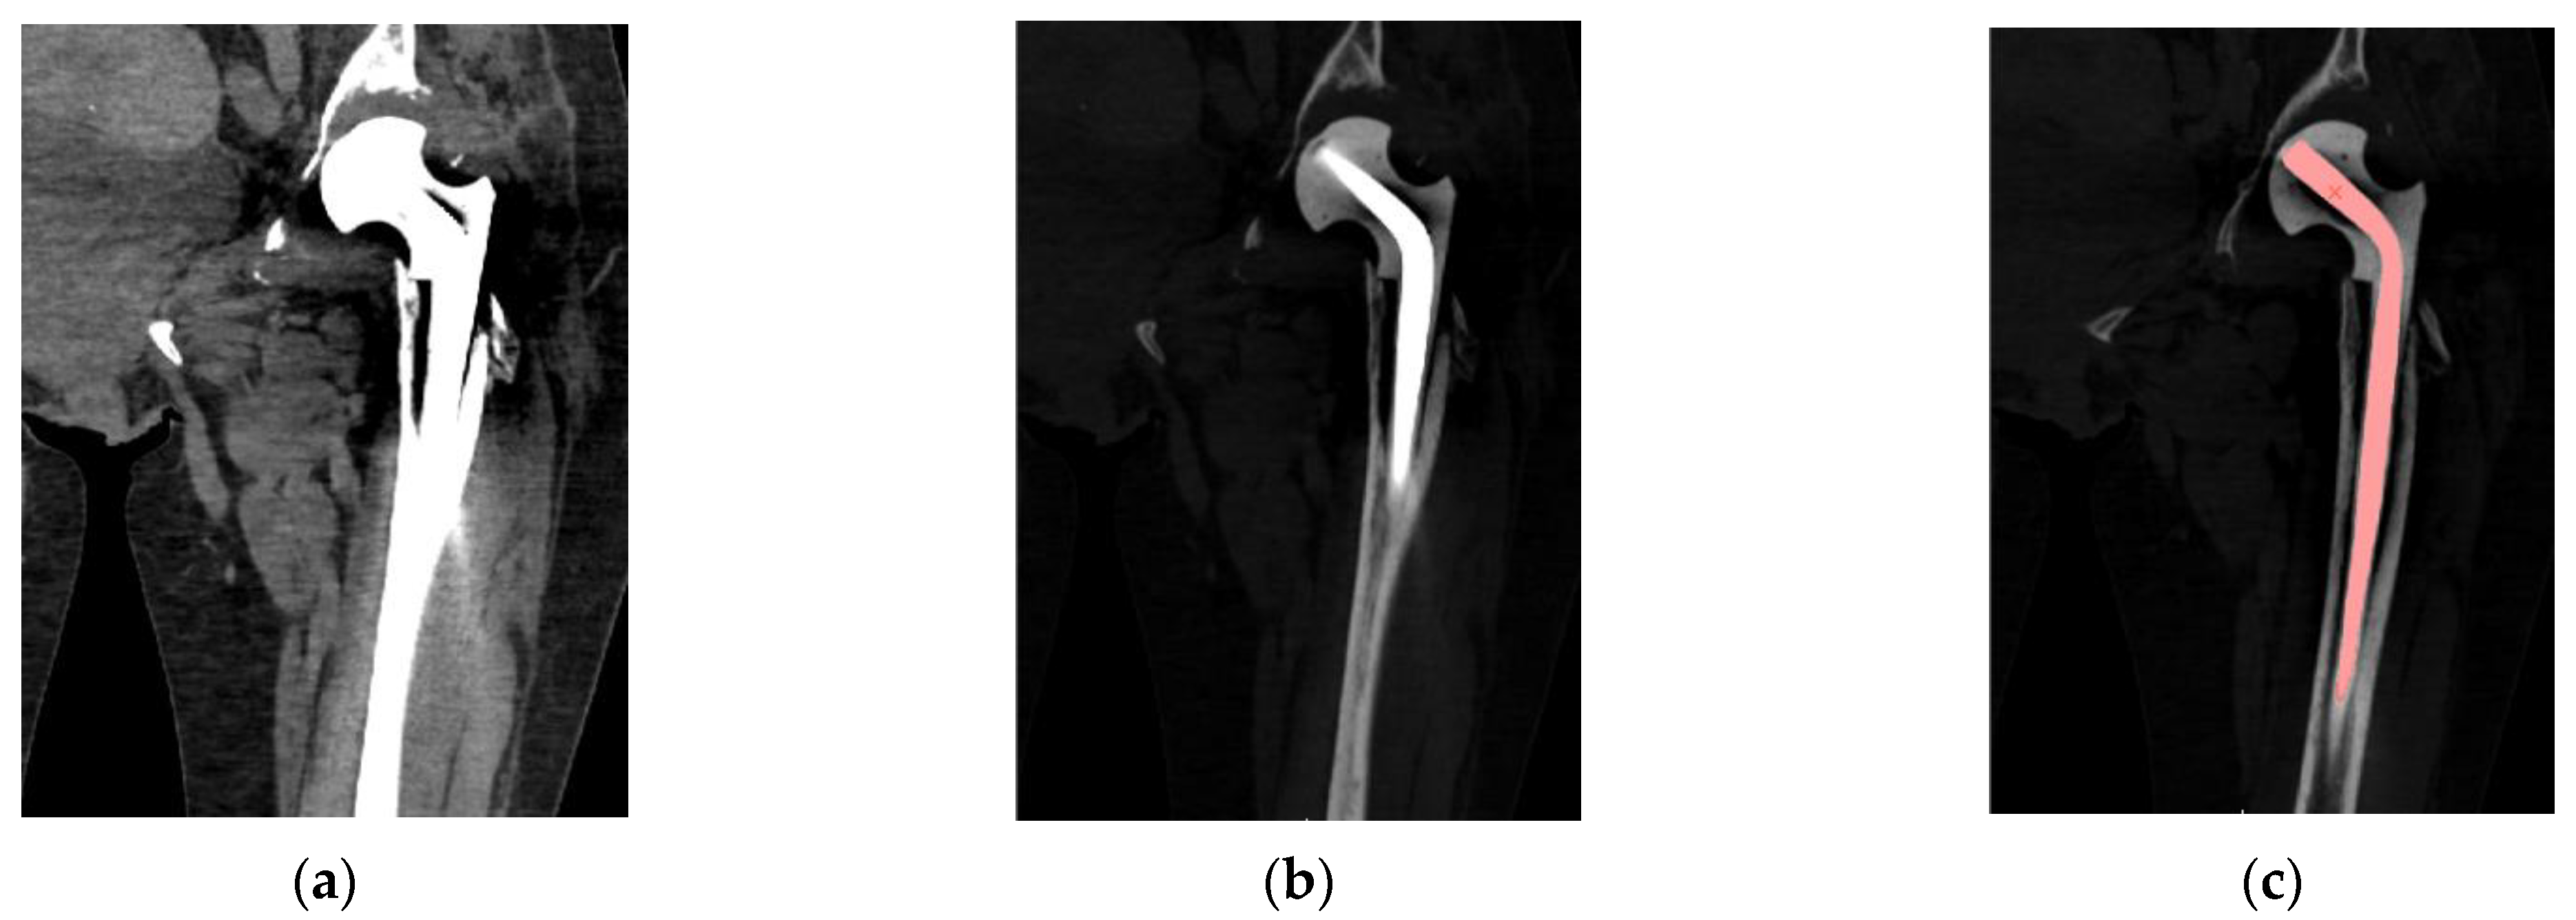

2.2. Segmentation and Reconstruction of the Geometry